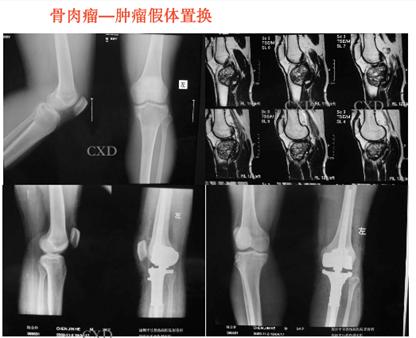

常见的良性骨肿瘤有骨样骨瘤、骨软骨瘤、软骨瘤等,原发性恶性骨肿瘤常见的有:骨肉瘤、软骨肉瘤、恶性纤维组织细胞瘤、尤因肉瘤、恶性淋巴瘤、骨髓瘤、脊索瘤等。

转移性骨肿瘤常见来源有:乳腺癌、前列腺癌、肺癌、甲状腺癌、肾癌。还有类肿瘤性的其他病损,包括骨囊肿、动脉瘤样骨囊肿、嗜酸性肉芽肿、骨纤维结构不良。其中青少年好发的恶性肿瘤最常见的是骨肉瘤、尤文肉瘤。

尤文氏肉瘤新辅助化疗后的保肢手术

骨巨细胞瘤(Capamnacci III级)复发肿瘤假体置换术